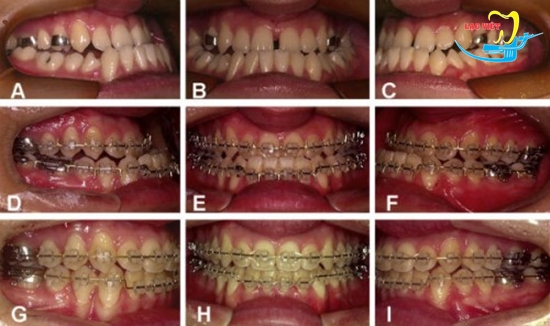

Niềng răng là phương pháp chỉnh móm mang lại hiệu quả tối ưu nhất

3. Hình ảnh trước và sau khi niềng răng móm tại nha khoa Lạc Việt

Một vài hình ảnh trước và sau khi niềng răng móm tại nha khoa Lạc Việt (*)

(*) Lưu ý hiệu quả khác nhau trong từng trường hợp cụ thể